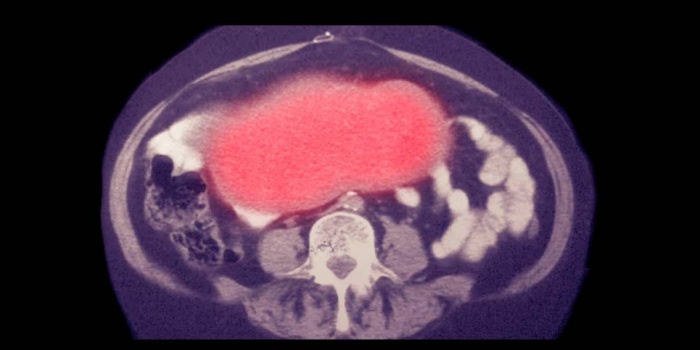

Yumurtalık kanseri belirtileri

The Guardian’da geçen habere göre, yumurtalık kanseri belirtileri sıklıkla şişmiş bir karına sahip olmayı veya şişkin hissetmeyi içerir. Karın veya pelviste ağrı o bölgede oluşan hassasiyet de bir belirtidir. İngiltere Ulusal Sağlık Hizmeti’ne (NHS) göre, yemek yedikten sonra iştahsızlık veya hızlı bir şekilde doyma hissi ve acil bir işeme ihtiyacı ya da sık idrara çıkma da bu bir belirtidir.

Ankette ayrıca, kadınların %40'ının yumurtalık kanserinin rahim ağzı kanseri taramasıyla bulunabileceği gibi yanlış bir kanıya sahip olduğu da tespit edildi. Yumurtalık kanseri, tanıdan sonraki ilk yıl içinde hastalığı olan kadınların yaklaşık üçte birini öldürür ve genellikle geç evrelerde teşhis edilir.